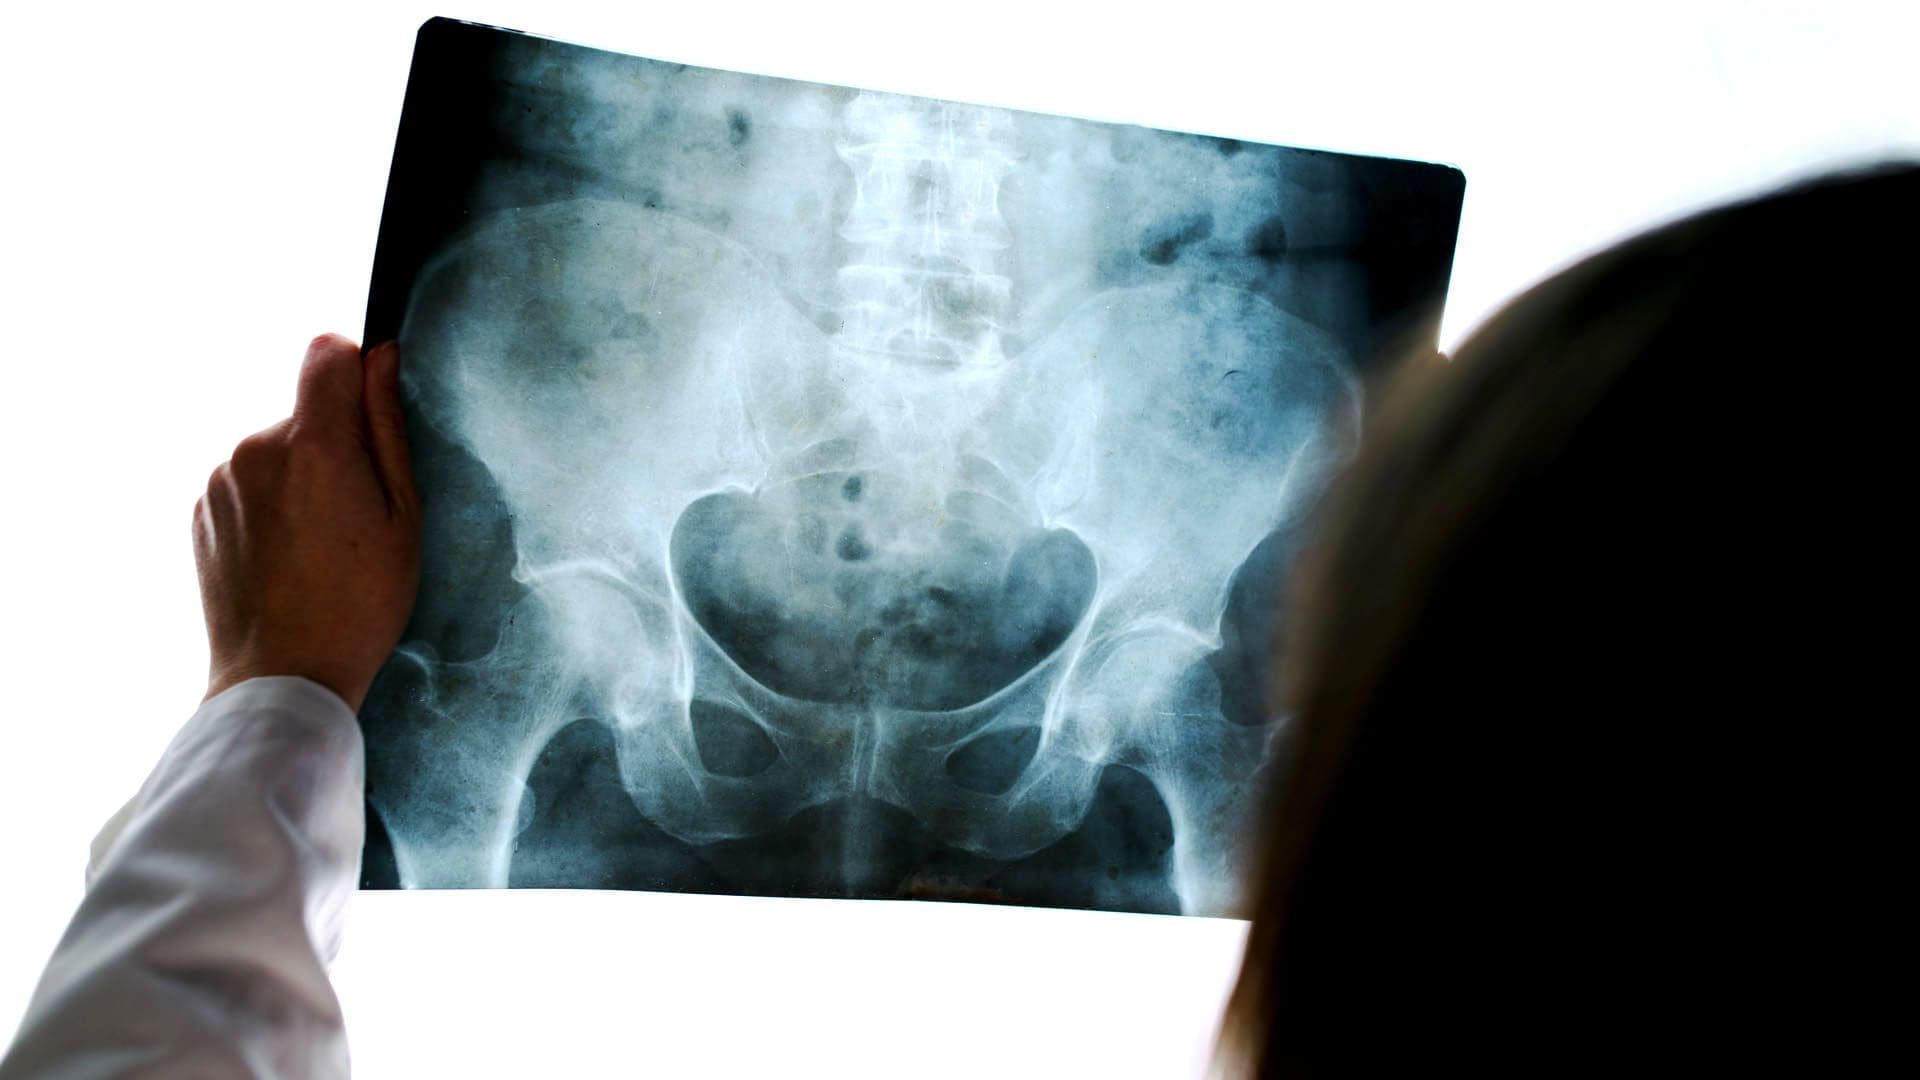

- AP pelvis: complete displaced Garden 4 Fx (above the second image)

- Clinical pearls: in some cases of Garden 4 Fx, DDx may be difficult to differentiate from OSP vs. pathologic fx d/t to bone Mets of Multiple myeloma (MM)